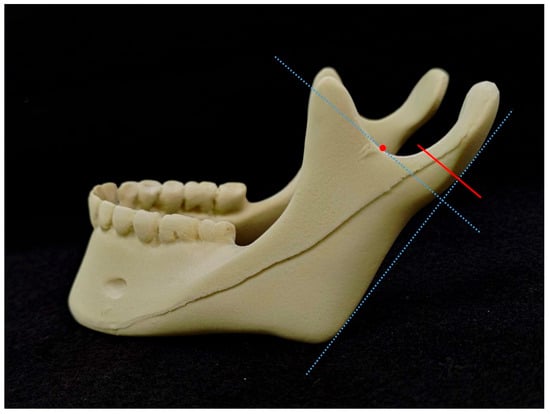

2. Materials and Methods

3. Results